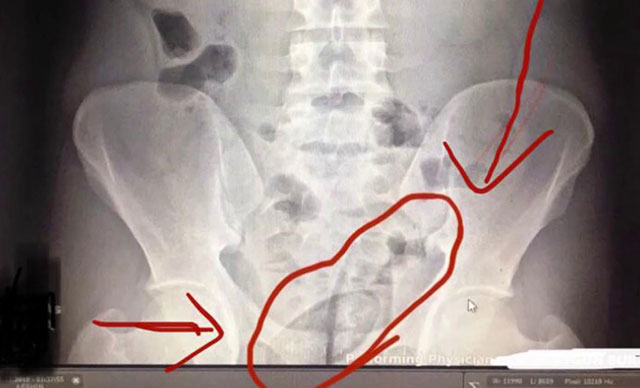

Kars'ta, İran uyruklu 2 şüphelinin bağırsaklarında, kapsül içinde 150 gram metamfetamin ve 30 gram kubar esrar taşıdıkları ortaya çıktı.  ...